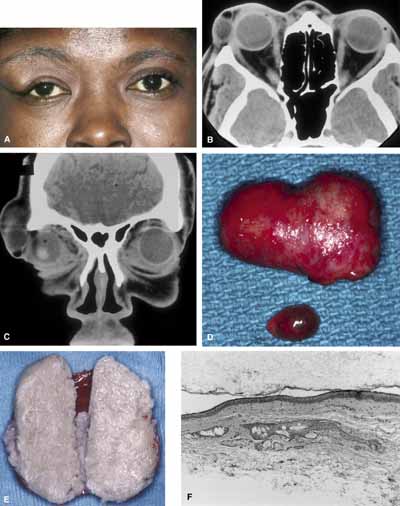

Typically, a dermoid cyst presents in a child as a mass protruding forward from beneath the superior orbital rim anterior to the orbital septum (Fig. 1). Dermoid cysts are found most commonly in the superotemporal quadrant and less frequently superonasally, but these cysts may occur elsewhere in the periobital region both anterior and posterior to the orbital septum and in the temporal fossa.

The usual cyst is a painless, smooth, ovoid-to-round, firm, rubbery mass. It may be mobile or immobile, being relatively free or firmly attached to the underlying bone (periosteum), but it is not attached to the overlying skin, distinguishing them from implantation cysts. Although contour abnormalities of the eyelid are common, there is little or no displacement of the globe with dermoid cysts located along the orbital rim. In an adult presentation, a dermoid cyst may frequently have a more posterior location.8 These posteriorly located cysts more typically present in adulthood, are more difficult to palpate, and proptosis and globe displacement are more common.

The nature of an orbital dermoid cyst can be demonstrated well by computed tomography (CT): the cyst has a low-density lumen and its relationship to the underlying bone is often manifested by smooth remodeling of the bone secondary to cyst expansion; the high content of fatty material within the cyst makes it radiolucent.

Because of the variable presentation of dermoid cysts, Shields et al.,5 have suggested a classification of orbital dermoid cysts by their association (or lack of association) with suture lines of the skull and assist the clinician in appropriate management. Cysts are classified as juxtasutural, sutural, or soft-tissue dermoid cysts. Those cysts adjacent to the bony suture line but not firmly attached are juxtasutural. A sutural dermoid cyst is firmly attached to bony sutures causing bone erosion, tunnels or an hourglass configuration. Soft tissue dermoid cysts may be strictly confined to soft tissues without any connection to a bone structure. Intradiploic epidermoid cysts are distinctly uncommon and were not included in Shields' classification (Fig. 3).

Surgical extirpation should be complete. Intraoperative rupture of the cyst with release of its contents into the orbit may incite a mild but smoldering granulomatous inflammation. The contents of these cysts may vary from an oily, tan liquid to a cheesy, yellow-white material. When inadvertent rupture occurs, the operating surgeon must flood the wound with irrigating solution to be sure that all this material has been washed away. Complete removal of the cyst wall is curative; incomplete removal may be followed by recurrence. Although marsupialization of deep and extensive dermoid cysts has been advocated by some practitioners,14 this technique is not recommended.8

Histologic study of all these cysts is recommended, because rare cases of epidermoid cysts undergoing malignant transformation into squamous cell carcinoma have been reported in adult patients.15 Although granulomatous inflammation may be seen histologically in as many as two-thirds of dermoid cysts removed in one large retrospective series, the clinical signs of inflammation are observed in the minority of patients.5,10